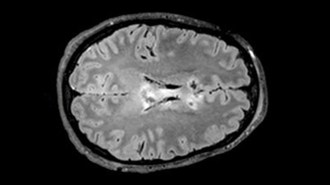

NeuroscienceA blood test may help predict recovery from traumatic brain injury

High levels of a key blood protein point to brain shrinkage and damage to message-sending axons, providing a biomarker for TBI severity and prognosis.